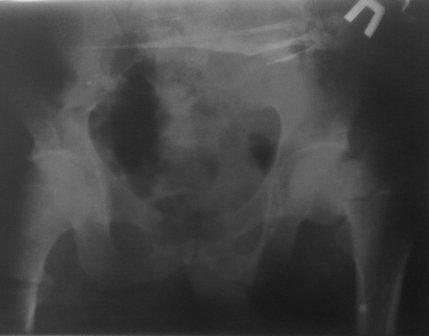

Чрезвертельный перелом бедра

Уважаемые коллеги. Больной 1980г.р. после тяжелой сочетанной травмы от 03.12.10г: спленэктомии, ушивание разрыва печени, мн.переломы ребер. 05.02.11г операция по поводу спаечной к/непроходимости. И чрезвертельный перелом правого бедра,

посмотрел под скопией сращения нет, при проверке двигается только дистальный отломок, а головка как бы припаяна к вертлуге. Укорочение ноги 5см, нога ротирована вовнутрь и приведена, из-за боли проверить объем движения не удается.

В плане PFN -ChM , но может быть контрактура т/б сустава, или делать открытым способом (тогда большая кровопотеря, и так он ослабленный), м/б предварительно аппарат таз-бедро или вытяжение большим грузом?

DHS ,blade plate кончились, имеется шеечные винты, Г-образные пластины ЦИТО-Бокачырева, и кое-что можно из пластин приспособливать по "гаражной ортопедии"